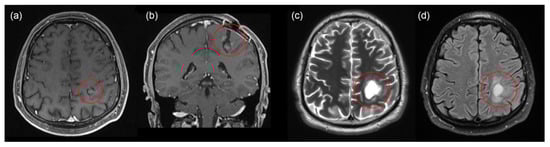

2.2. Second Intervention

2.3. Third Intervention